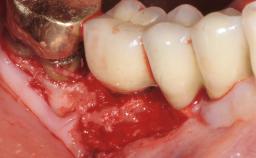

Late Presentation of Peri-Implant Mucositis Requiring Soft-Tissue Augmentation and Esthetic Crown Lengthening at Implant Site 11

Eduardo R Lorenzana, Jason R Gillespie

Biological or technical complications around implant-supported prostheses place a significant burden on patients as well as the surgical and restorative team. Inflammation of the peri-implant soft tissues is often the first sign that something has gone awry. While there is never a good time for a complication, late presentation of inflammation in the soft tissues around a long-standing prosthesis triggers a period of research and review of the case in order to ascertain the treatment history and its possible contribution to the etiology of the situation. This becomes more complicated in situations where a patient has not received regular maintenance and clinical/radiographical examinations due to personal, financial, or professional reasons. When the complication occurs in the esthetic zone, the complexity of the situation expands exponentially, as the only acceptable outcome in the patient’s eyes will be the maintenance of the esthetics of the prosthesis.